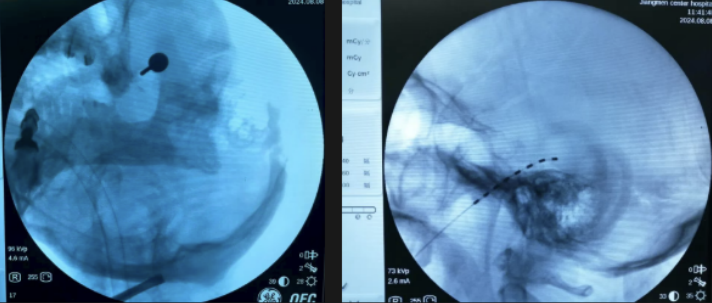

2.三叉神经半月节微球囊压迫术

三叉神经痛素有“天下第一痛”之称。经皮三叉神经半月节微球囊压迫术是一种微创治疗技术,无需开颅,通过穿刺将微球囊置入三叉神经半月节区域,短暂压迫以阻断异常痛觉传导,具有创伤小、风险低、起效快、疗效确切、疼痛缓解维持时间长等优势,现已成为治疗顽固性三叉神经痛患者的首选治疗方案之一。

我院疼痛科自2022年开展此项技术以来,已成功为近百例患者实施手术,临床效果显著,术后疼痛缓解率高,且无一例发生严重并发症。

△三叉神经半月节微球囊压迫术

我院疼痛科于2022年1月成功实施江门地区首例脊髓电刺激植入术,为一位60岁饱受30余年神经痛及幻肢痛困扰的患者带来显著缓解;2024年8月,又率先完成五邑地区首例三叉神经半月节电刺激系统植入术,进一步拓展了神经调控技术在头面部顽固性疼痛中的应用,标志着我院在慢性疼痛微创与神经调控治疗领域持续走在区域前列。

△三叉神经半月节电刺激植入术